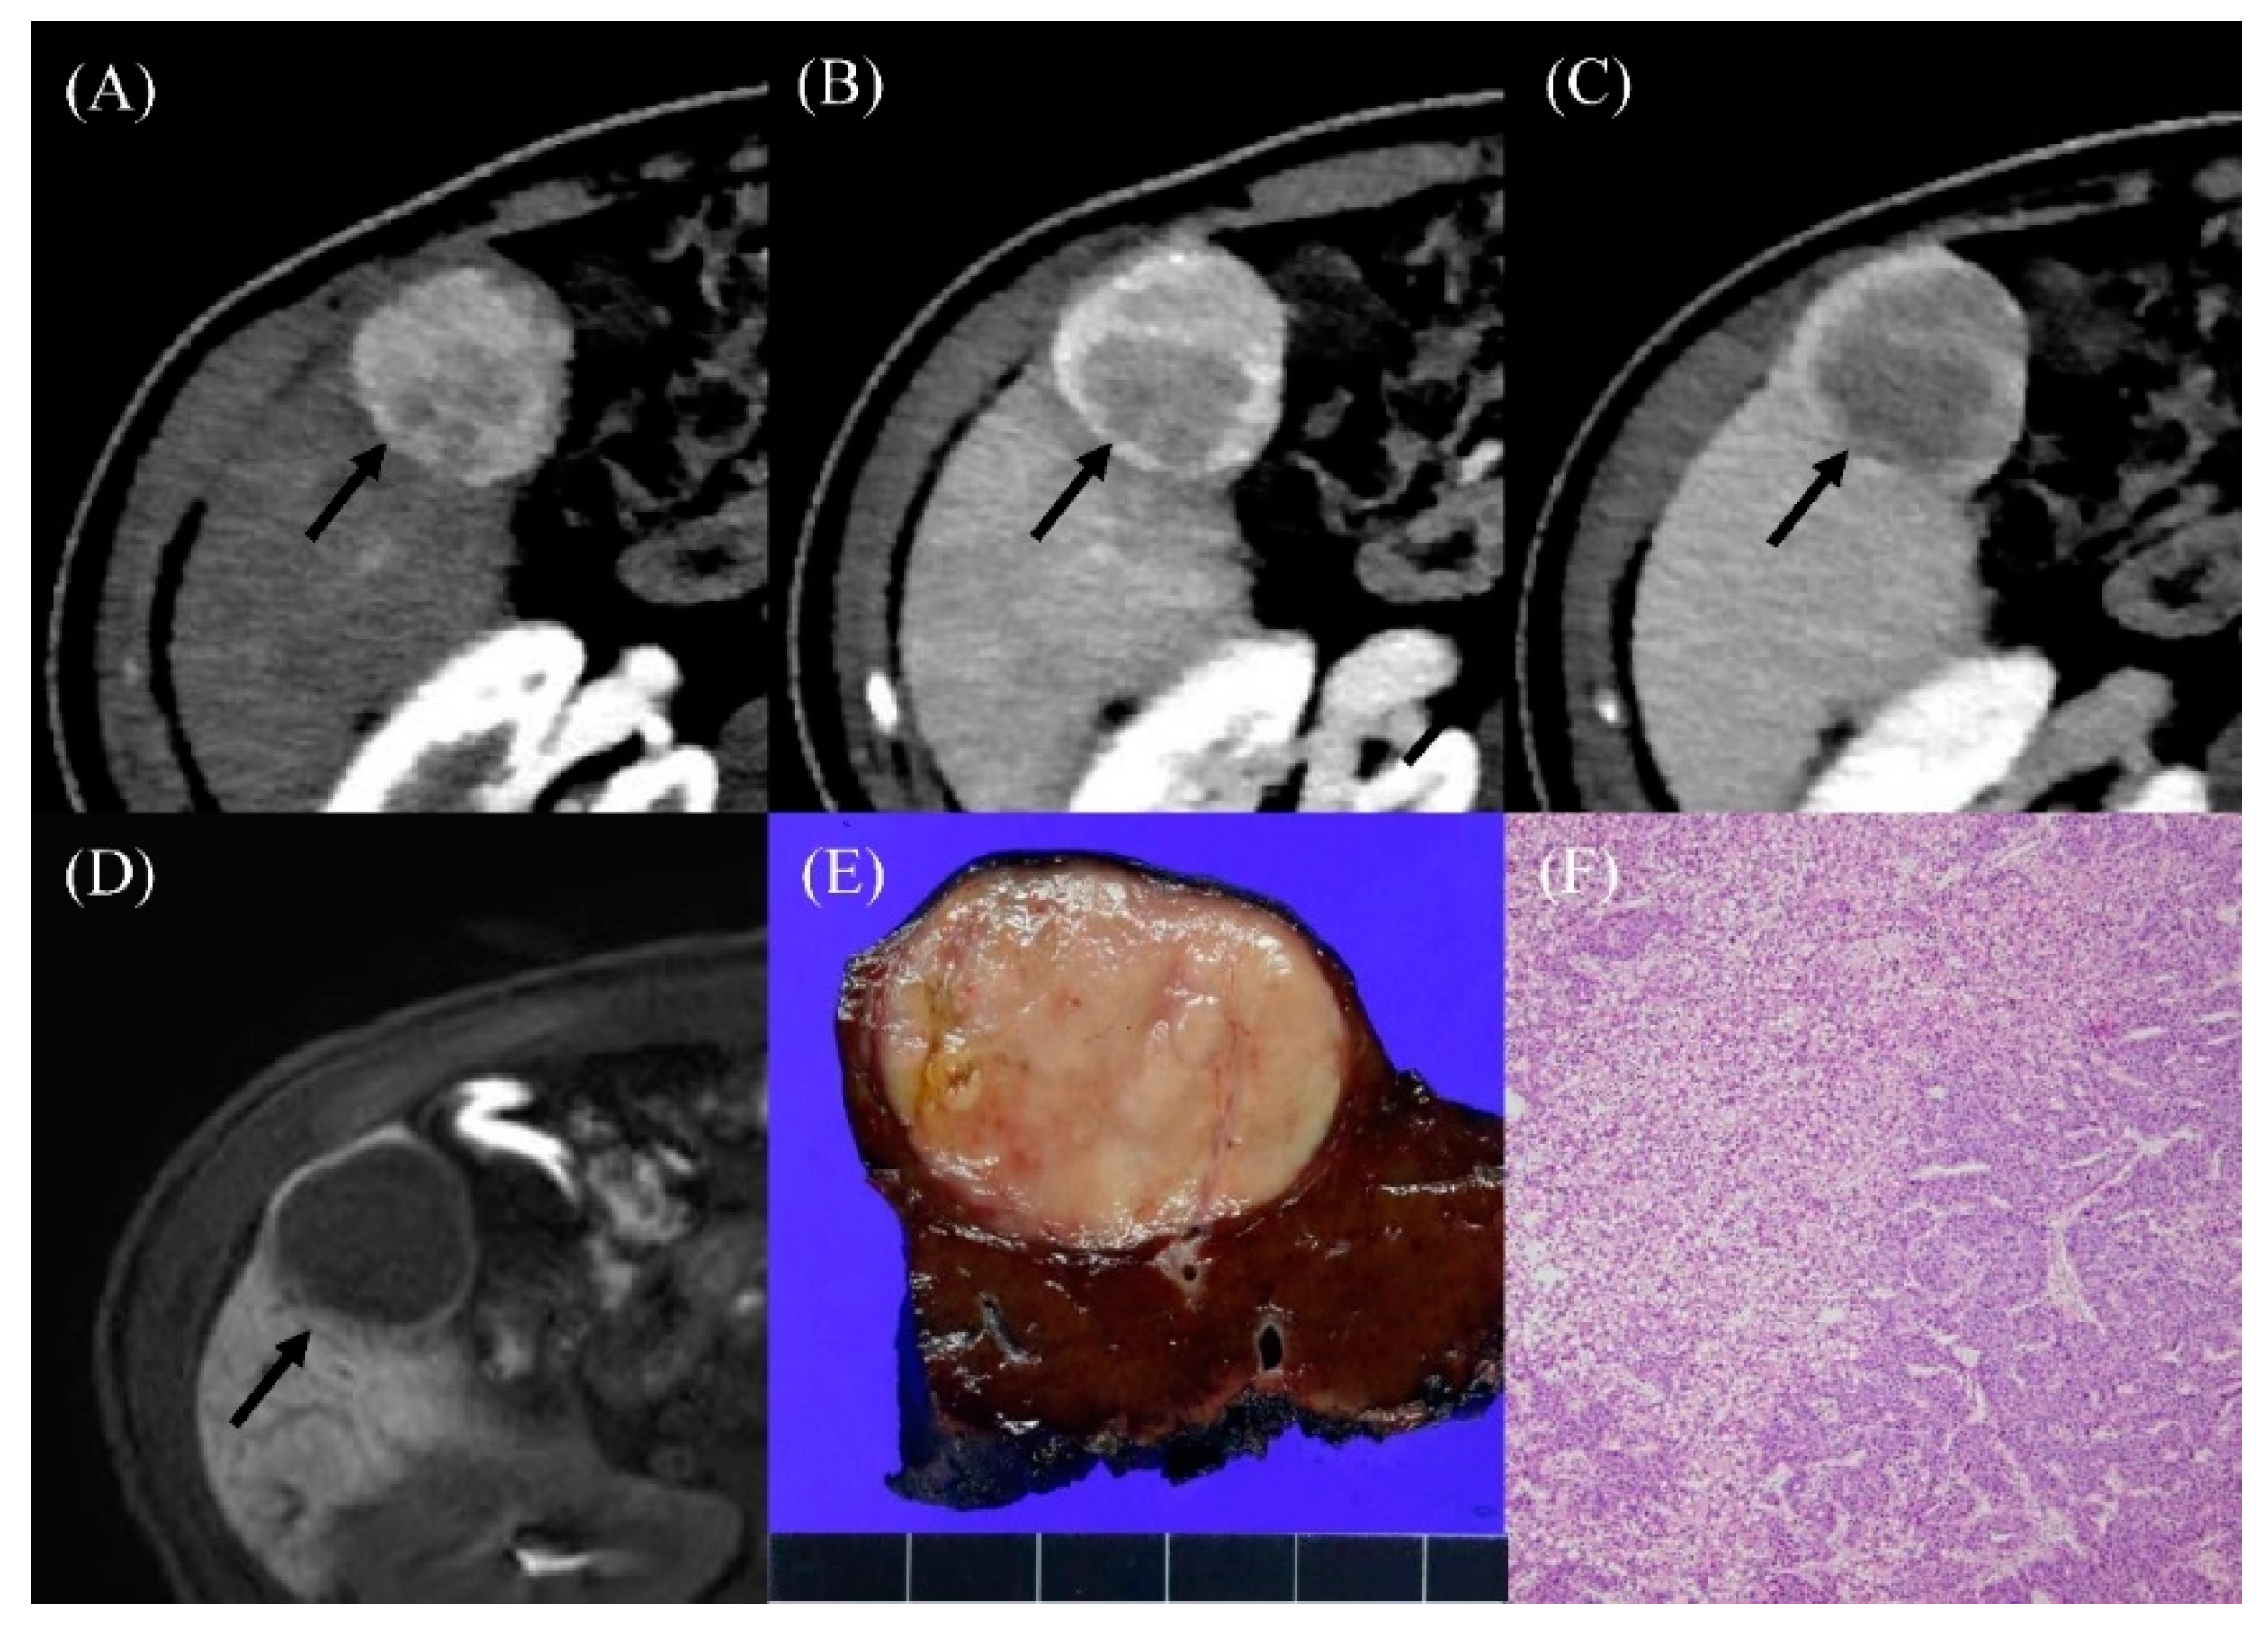

2.4. Development of HCC

2.5. Features Distinguishing HCC from Benign APHE Nodules